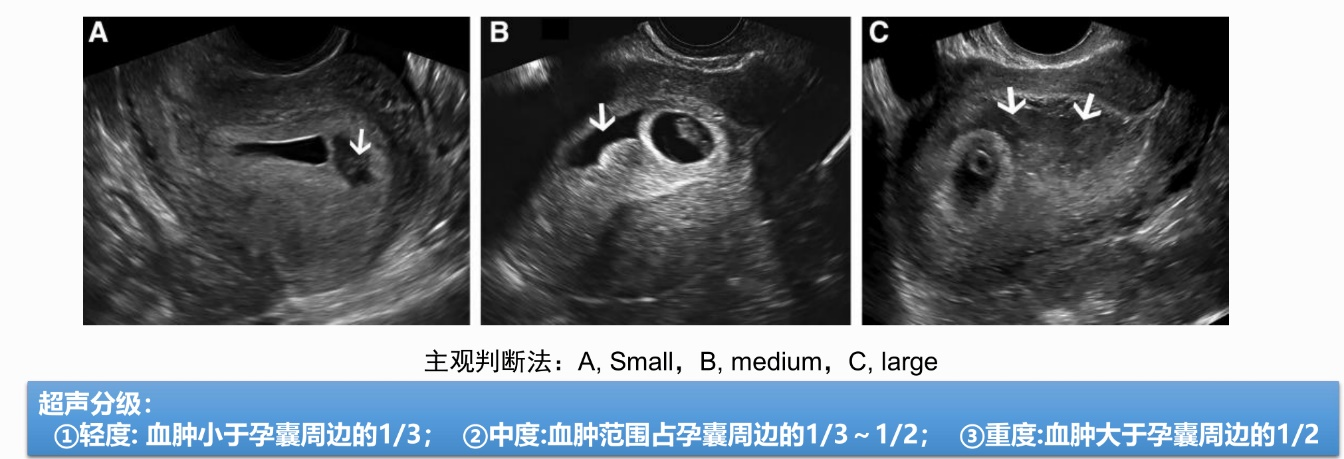

宫腔积液按照出血面积(体积)分为轻、中、重三型。轻型:出血面积<孕囊面积的1/3;中型:出血面积为孕囊面积的1/3-2/3;重型: 出血面积>孕囊面积的2/3。